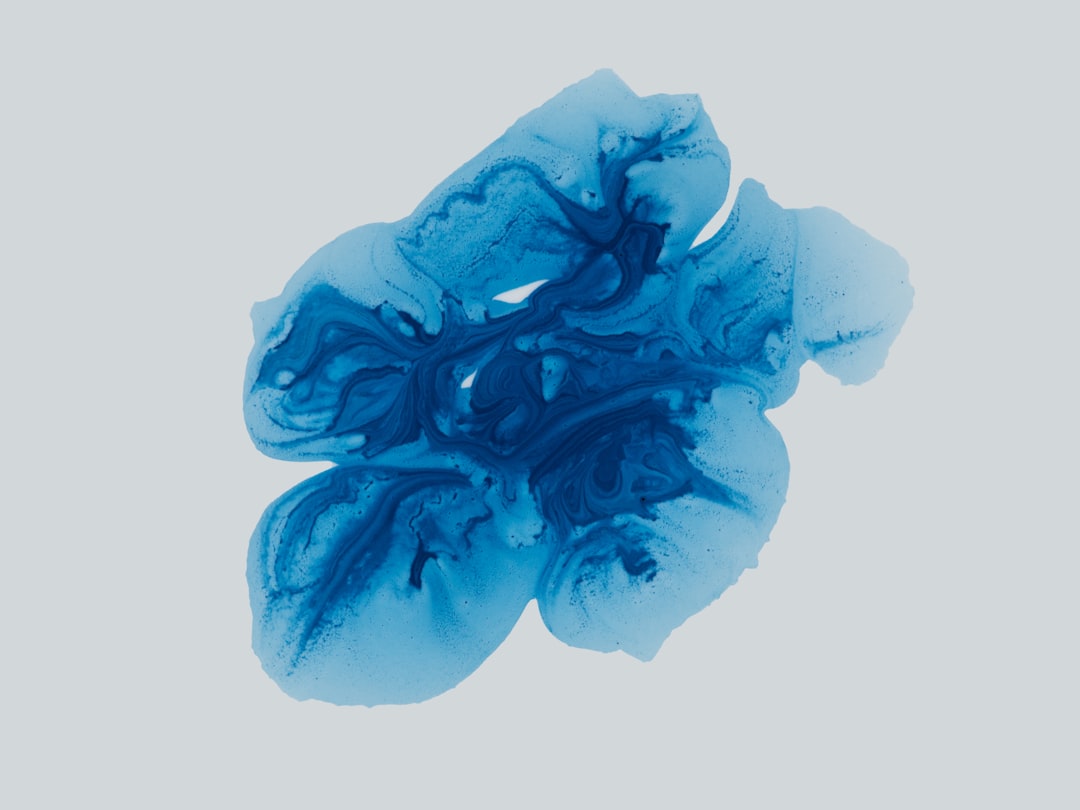

당뇨 발저림은 당뇨병 환자들 사이에서 흔히 나타나는 증상 중 하나로, 주로 발에 저림이나 감각 이상의 형태로 나타납니다. 이 증상은 당뇨병으로 인한 신경 손상에 기인합니다. 특히 고혈당이 지속되면서 혈관이 손상되고, 그로 인해 신체의 신경이 제대로 기능하지 않게 되는 것입니다. 개인적으로 경험해본 바로, 이러한 증상은 삶의 질을 크게 저하시킬 수 있습니다. 우리는 발저림이 있을 때, 간단한 일상생활조차 힘들게 느껴질 수 있으니까요.

당뇨 발저림의 발생 원인은 주로 높은 혈당과 관련된 신경 손상입니다. 혈당이 고갈되면 신경 조직이 손상되기 시작하고, 이는 신경 말단의 기능 저하를 초래합니다. 물론, 이러한 신경 손상은 전체 신경계에 영향을 미치며, 종종 제가 생각하기에도 이는 매우 불편한 경험으로 이어집니다.